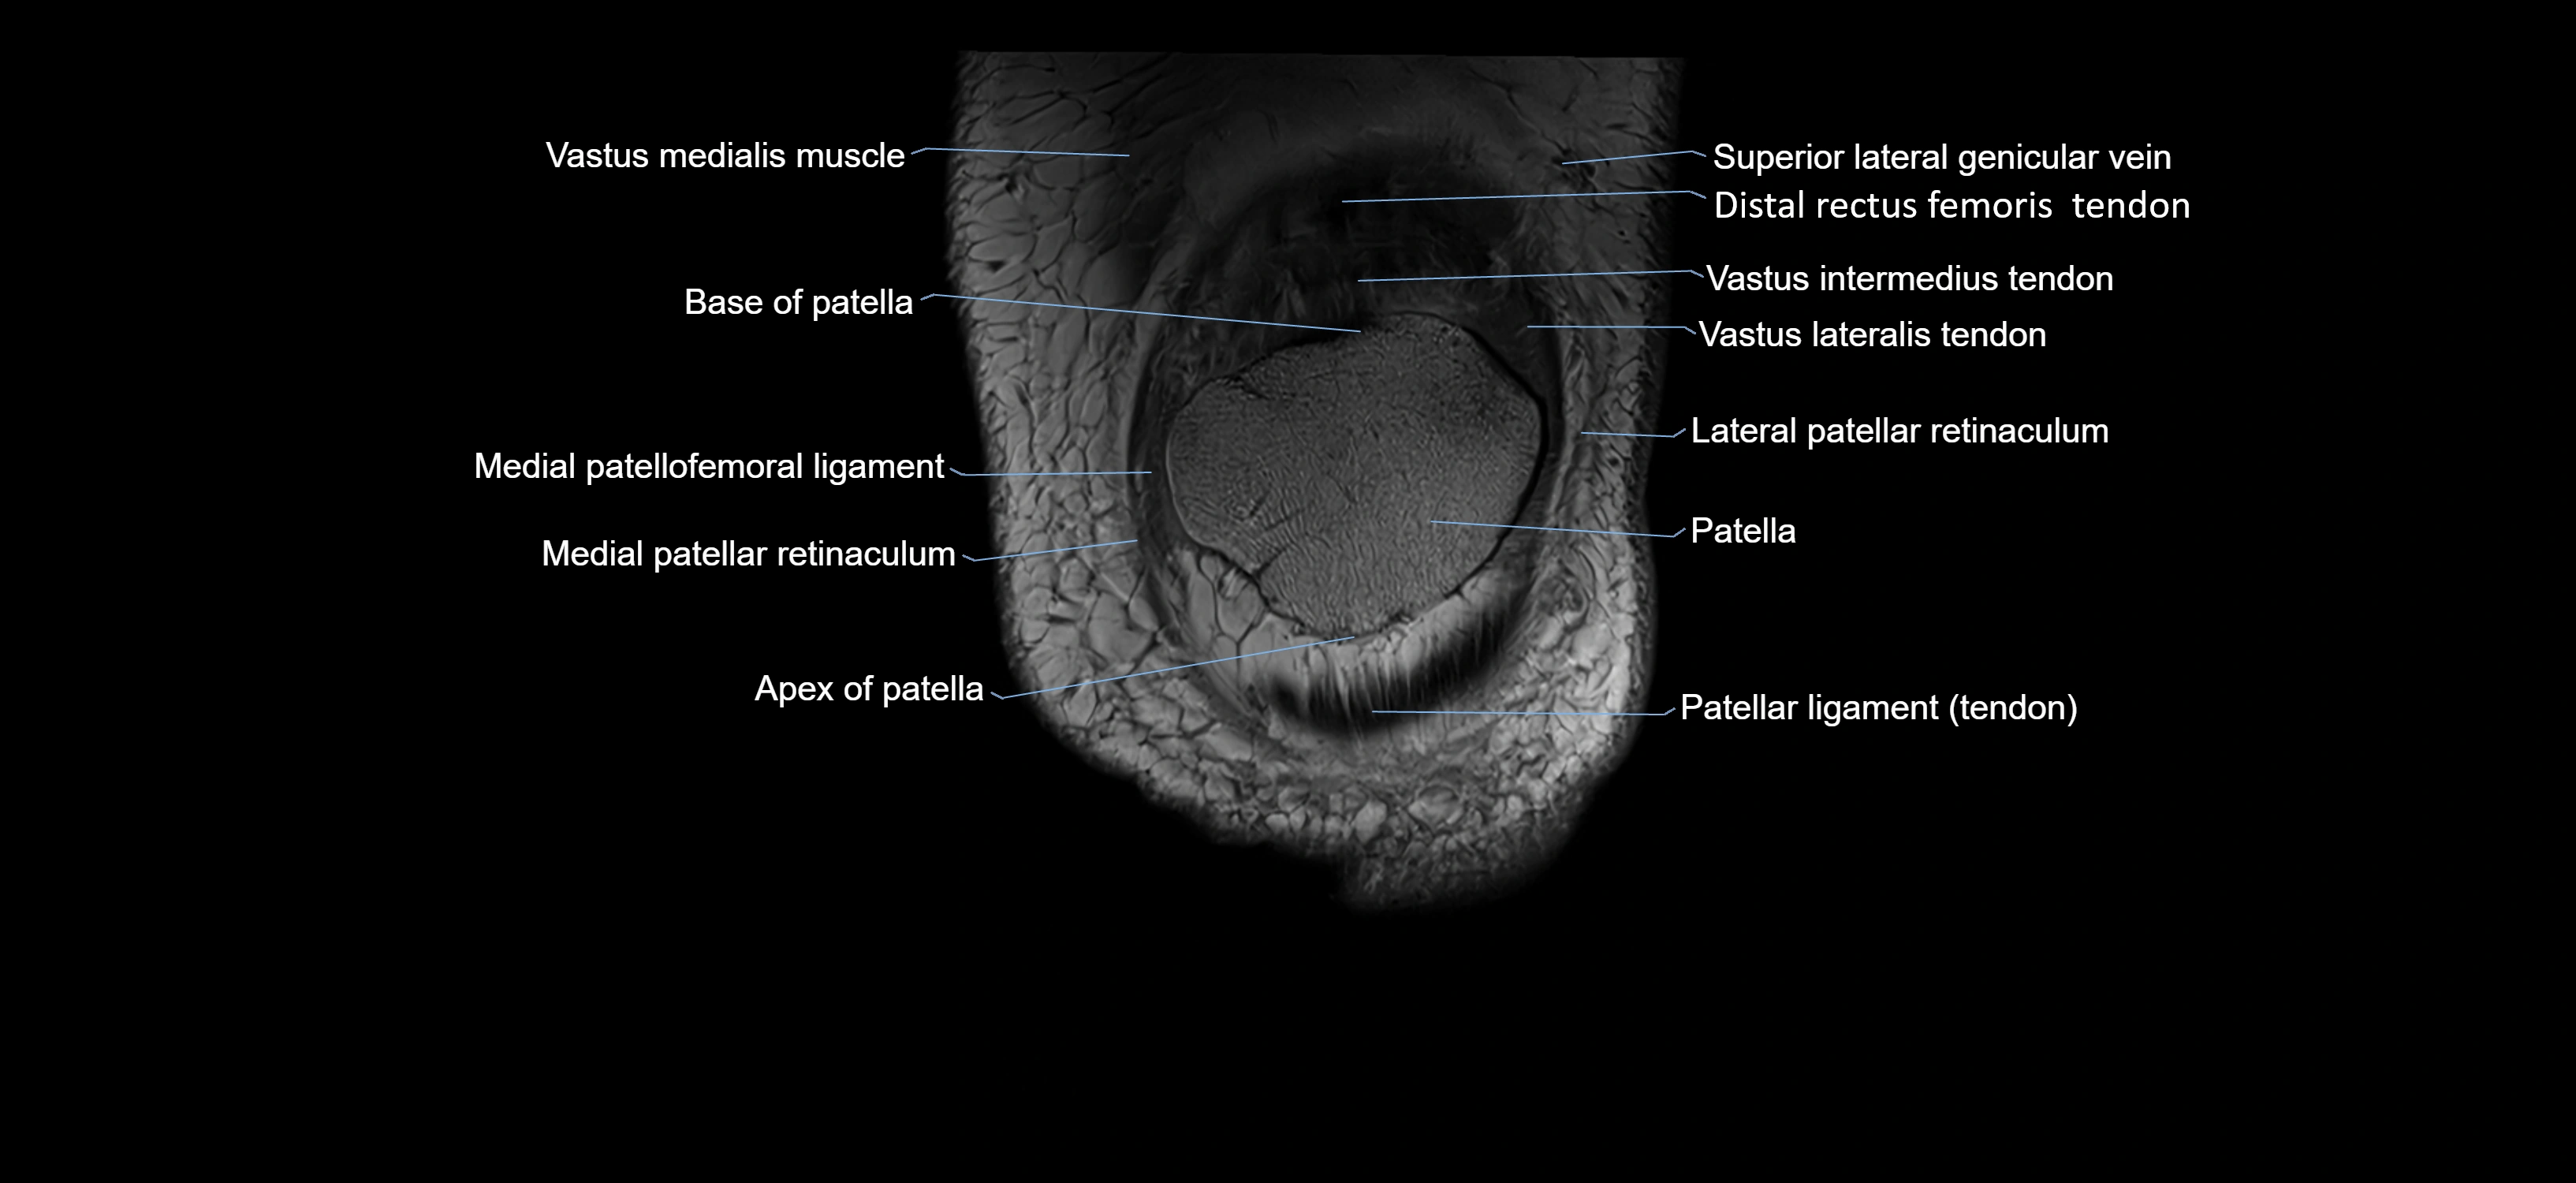

- Apex of patella

- Base of patella

- Lateral patellar retinaculum

- Lateral patellofemoral ligament

- Medial patellar retinaculum

- Medial patellofemoral ligament

- Patella

- Patellar articular cartilage

- Patellar tendon (patellar ligament)

- Superior lateral genicular vein

- Distal rectus femoris tendon

- Distal vastus intermedius tendon

- Distal vastus lateralis tendon